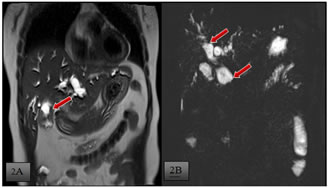

A 45 year old female presented with chief complaints of pain abdomen, non bilious, non projectile vomiting, yellowish discolouration of the skin and eyes with high colouredurine for one month. She also complained of itching over the body. Physical examination revealed presence of icterus and tenderness in the right hypochondrium. A clinical diagnosis of obstructive jaundice was made. No history of any comorbid conditions present with past surgical history of hysterectomy. After routine blood investigations, which revealed increased bilirubin levels, radiological investigations done. Ultrasound of abdomen was performed which showed CBD stricture at the terminal end, grossly thickened gallbladder and peripancreatic lymphadenopathy. Side viewing UGI scopy was done which was normal. To further characterize the ultrasound findings, CECT abdomen was done which showed wall thickening (maximum thickness of 8 mm) noted involving the fundus and body of the gallbladder, irregular and nodular, more on the right lateral aspect with evidence of heterogenous enhancement seen on contrast administration.[Fig-1A] There is no clear fat plane seen between the gall bladder and the liver (segment IV and V), however there is no extension into the liver. Pericholecystic fat stranding seen and minimal pericholecystic fluid seen. Medially it is seen to abut the pylorus of the stomach and first part of the duodenum with no clear fat plane. Posteriorly there are areas of fat stranding seen extending up to the hepatic flexure of the colon. Also there was gross dilatation of the intrahepatic biliary radicles, the common hepatic duct, cystic duct and proximal common bile duct ( measuring 2.4 cm).There is an abrupt tapering at the junction of the mid and distal CBD duct ( just above the intrapancreatic segment) with suggestion of shouldering. [Fig-1B].There is short segment wall thickening (maximum thickness of 4.2 mm) noted in the distal CBD (intrapancreatic segment) for length of approximately 1.7 cm showing enhancement on contrast administration. The distal most CBD and the ampulla were spared. The rest of the intrapancreatic segment of the common bile duct appears normal. This thickening was seen well away from the gall bladder mass. There was no radiological evidence of contiguity noted. MR-Cholangiopancreaticography was done which showed an assymetrical wall thickening involving fundus and body of gall bladder with abuttment of adjacent liver and no infiltration [Fig-2A].Few stranding from the GB wall thickening to the hepatic flexure is seen. Abrupt narrowing with shouldering in the proximal CBD just after insertion of cystic duct and resultant severe upstream dilatation of biliary system [Fig-2B] A pre-operative diagnosis of gall bladder carcinoma with separate CBD involvement was made with possible diagnosis of same primary with skip involvement or synchronous malignancies. Then patient was subjected for pancreaticoduodenectomy [whipples procedure]. Post operative histopathology of the specimens revealed moderately differentiated adenocarcinoma of both gallbladder [Fig-3A] and the distal CBD [Fig-3B]with signet cell formation [15%] [Fig-3C].Margins free of tumour.

Figure 1A: CECT whole abdomen, coronal venous phase shows- Irregular and nodular heterogenous enhancingwall thickening involving the fundus and body of the gallbladder,, more on the right lateral aspect. Medially it is seen to abut the pylorus of the stomach and first part of the duodenum with no clear fat plane. Figure 1B: CECT whole abdomen, sagittal venous phase shows- gross dilatation of the intrahepatic biliary radicles, the common hepatic duct, cystic duct and proximal common bile duct with abrupt tapering at the junction of the mid and distal CBD duct ( just above the intrapancreatic segment) with suggestion of shouldering; Figure 2A: T2 haste MRCP coronal image shows assymetrical wall thickening involving fundus and body of gall bladder with abuttment of adjacent liver and no infiltration; Figure 2B: T2 3D-MRCP shows abrupt narrowing with shouldering in the proximal CBD just after insertion of cystic duct and resultant severe upstream dilatation of biliary system.